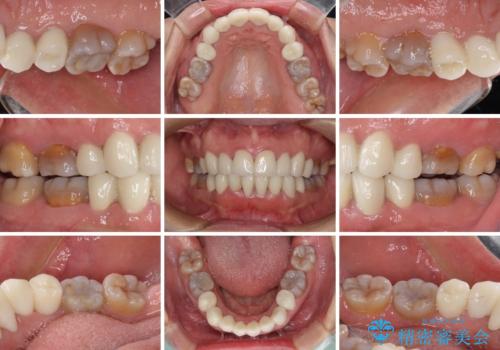

- 小さいころからの歯の変色と矯正治療の後戻りを気にして来院された患者様です。

気になる変色歯を仮歯に変え、その後歯列不正を矯正治療で改善し、最後にオールセラミッククラウンにて補綴治療することとしました。